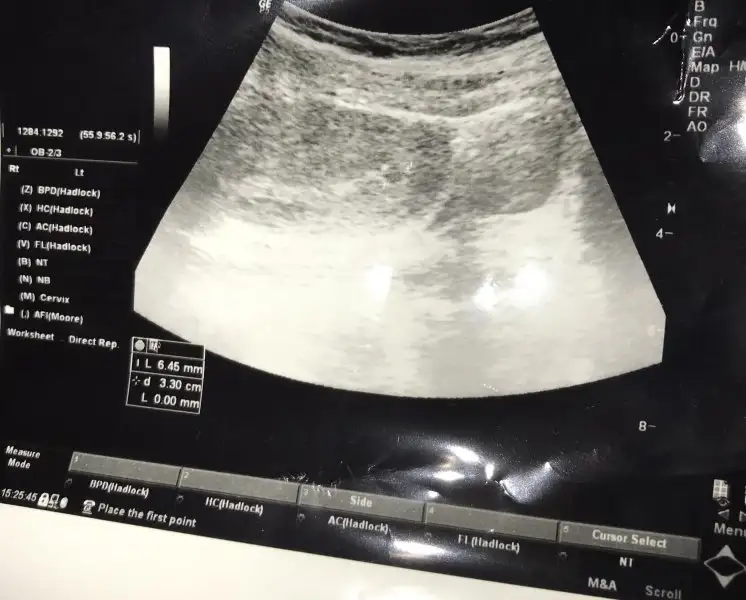

Kızlar dayanamadım gittim bi doktora. Sevdim sayılır doktoru. 5+4 bugün kese çok silikte olsa göründü. 3 hafta sonra hemen hemen kalp atışı diyor çok değil mi ya Geç döllenme tamam ama baya bi geriden geliyorum sanırım. Çok sancım herhangi bi lekelenmem olursa progestan verdi. Bi hafta sonra kontrol. Fotoya bakar mısınız mm nasıl oluyor ne ifade ediyor. Ben bunları unutmuşum hep ya

Eklentiler

• F6C79D84-DCB0-412B-A0FD-72023416F4E4.webp

28,2 KB · Görüntüleme: 123